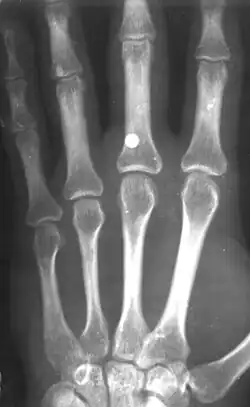

Верхний ряд — 5,5 мм (.22 дюйма), нижний — 4,5 мм (.177 дюйма)